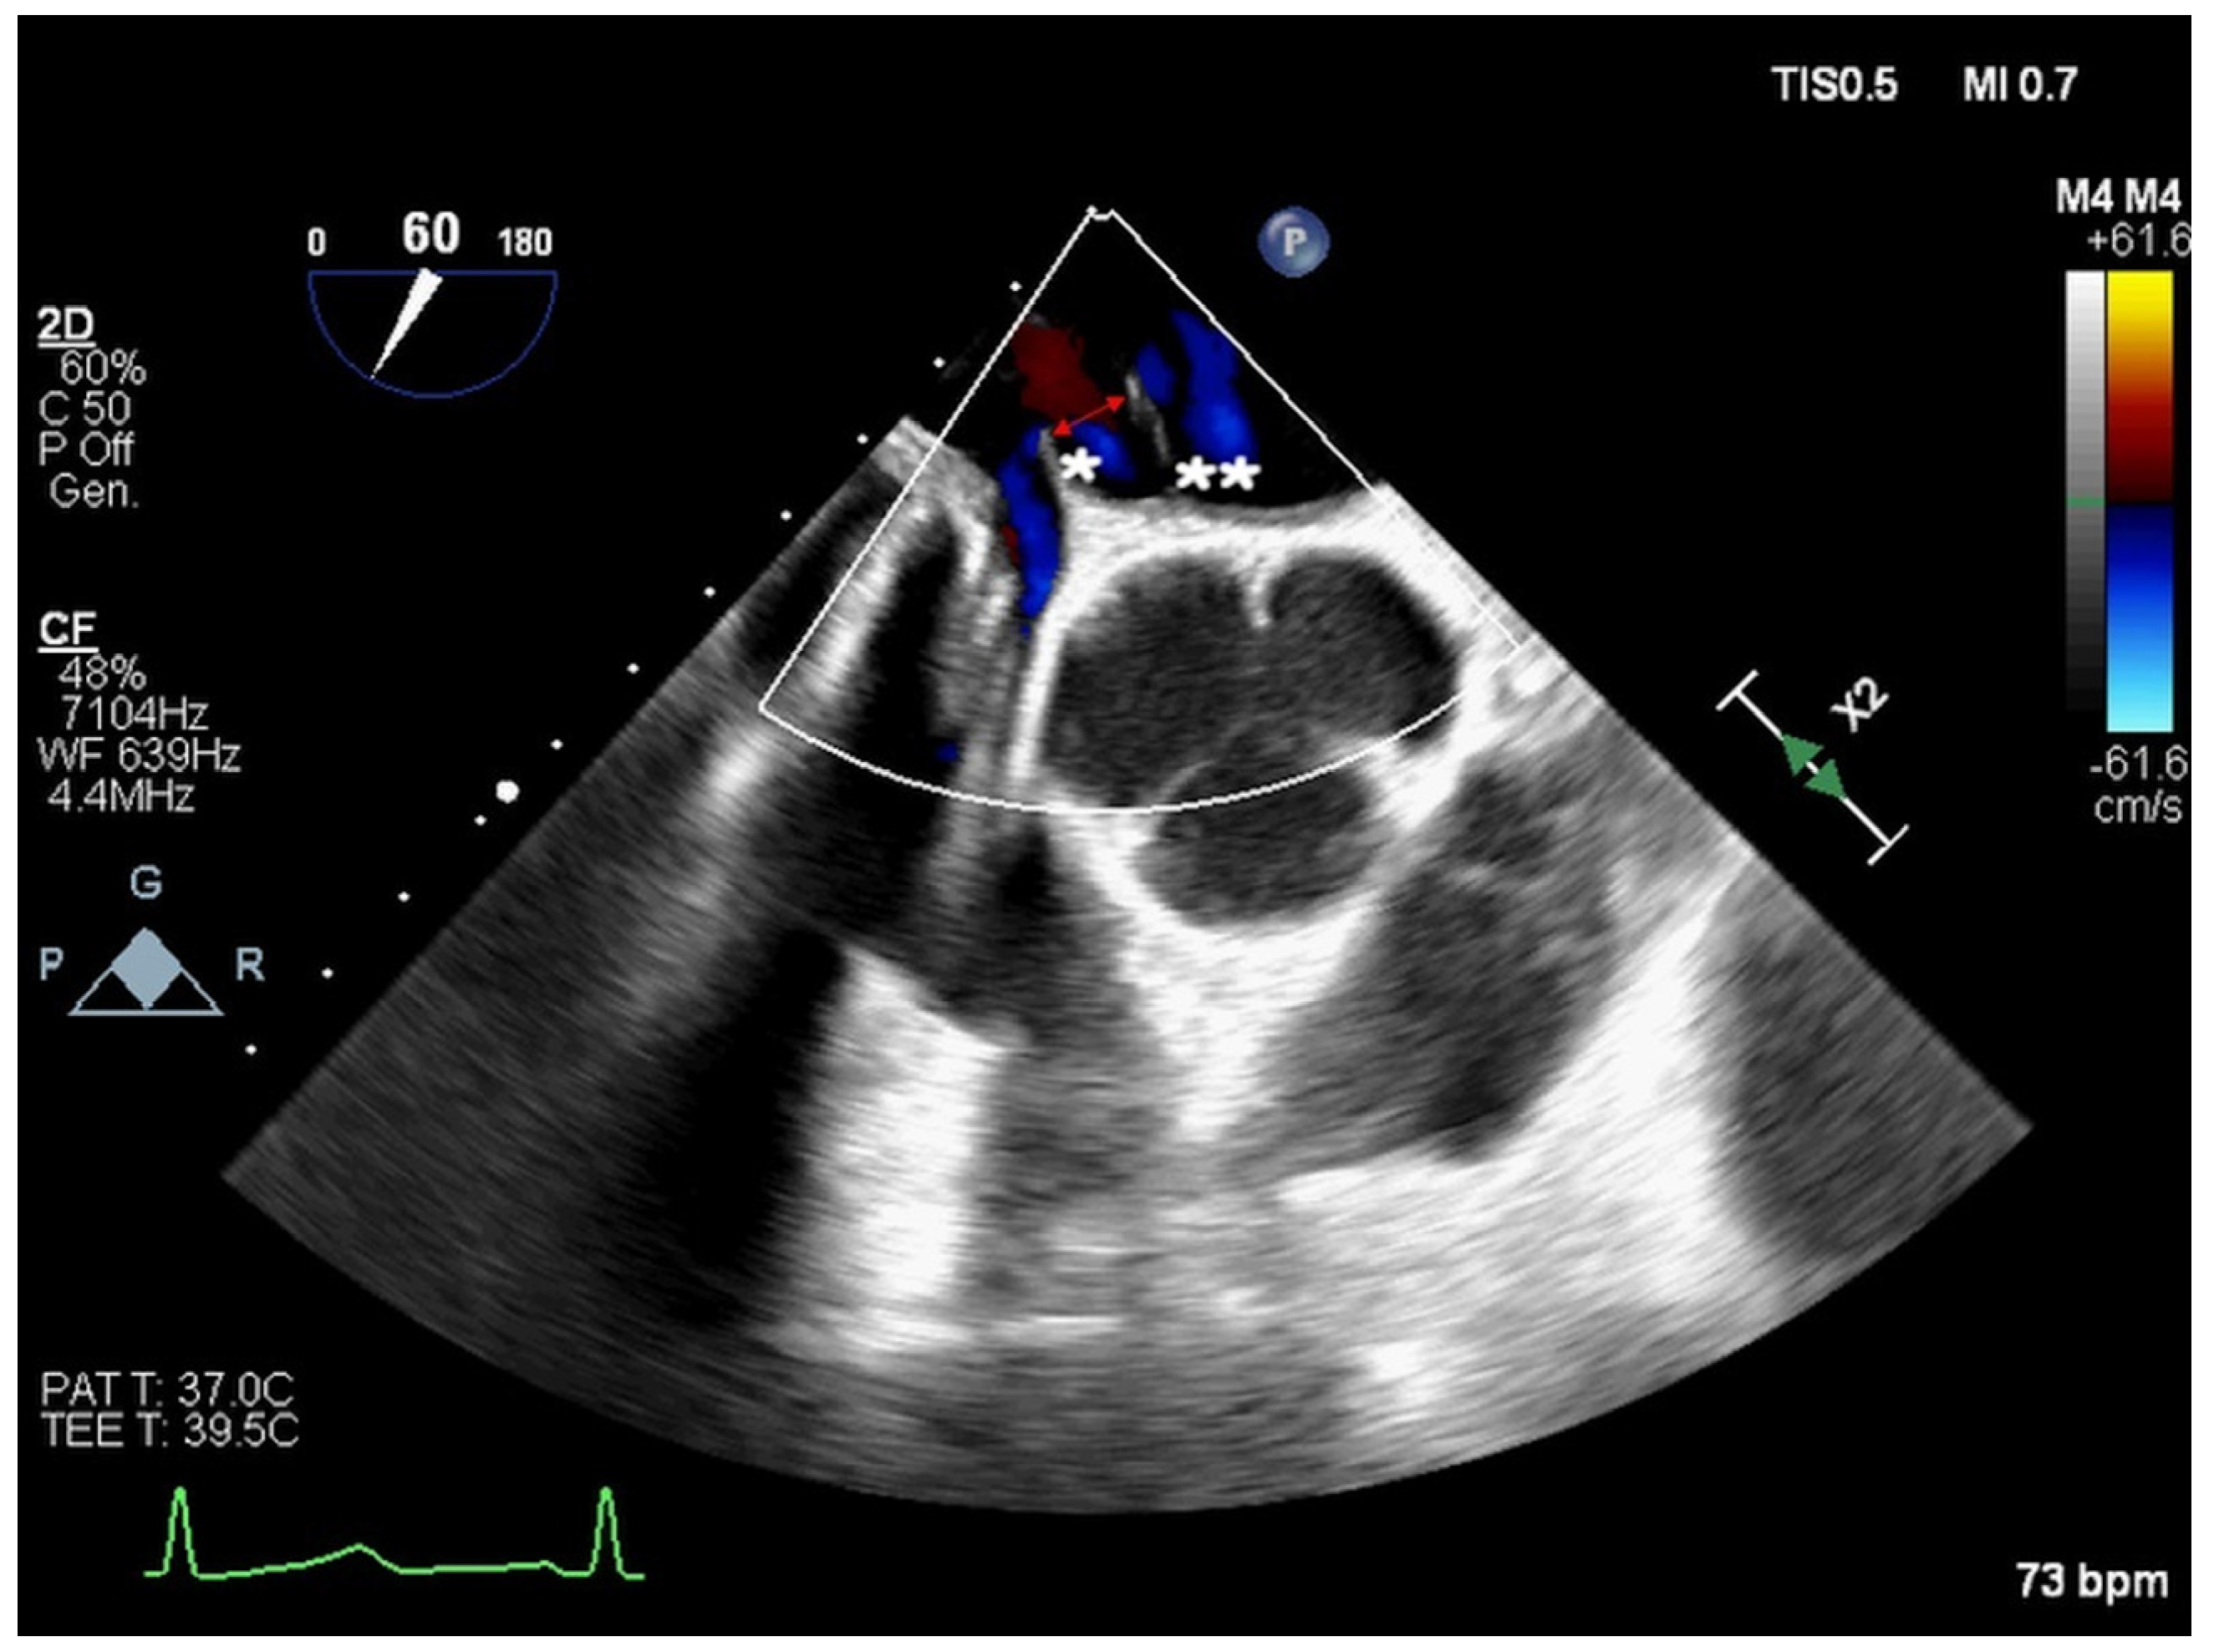

2. Atrial Septal Defect Closure

| ASD Closure: Pre-Procedural Assessment | |

|---|---|

| ASD shape | elliptical, round or irregular shapes (star-, reniform- or other irregular shapes), internal seedings |

| ASD size | maximum ASD diameter |

| ASD shunt direction | left-to-right, bidirectional, or right-to-left |

| ASD periorificial rims | adequate (>5 mm), poor (<5 mm), or absent |

| Accessory ASDs | numbers, size, and distance (if present) |

| Atrial septum aneurysm | base width and an aneurysm excursion into the right or left atrium (if present) |

| Misaligned ASD | distance of separation between the septum primum surface and the septum secundum one (if present) |

| Double atrial septum | separation between the left atrial and right atrial rims of the defects (if present) |

| Redundant Eustachian valve | length and excursion (if present) |

| Chiari network | width and extension (if present) |